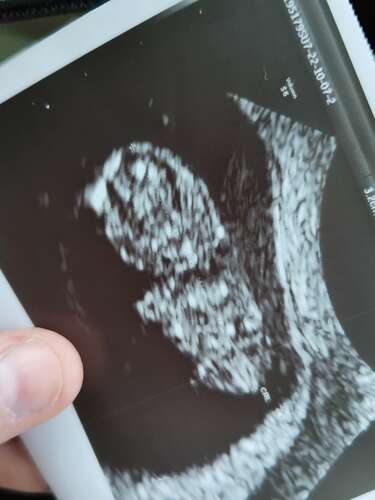

Dankjewel !! 😘😘 Had je ook klonters ? Aaaaah als je test donkerder was na de bloeding is het gewoon goed waarschijnlijk hoor !! Ik had echt helderrood zoals een gewone menstruatie. En ook best veel vond ik toch ... Je kan ook gewoon innestelingsbloeding hebben gehad. Dan schelen we een 3 tal weekjes of 3.5. leuk !! Ook lekker kort ertussen zeg zalig !! Ik ga duimen dat jou week heel snel mag omgaan !! En nog meer dat het gewoon prachtig nieuws is !! Dit is de laatste echo van onze schat met 8.6 weken